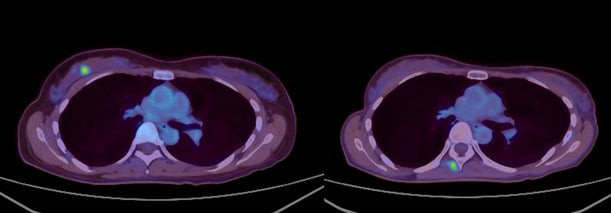

・FDG-PET陽性の浅在性腫瘍に対するBNCT(jRCTs031240204)治療4例目:再発乳がん

治療前約37mmの腫瘍が、治療3カ月後の画像診断で消失しています。

また、もともと基準値内(25以下)だった腫瘍マーカー(CA15-3)は20.9から10.7まで低下しています。

・FDG-PET陽性の浅在性腫瘍に対するBNCT(jRCTs031240204)治療10例目:初発乳がん(未手術)

FDG-PETにおける集積がSUV5からSUV1へ低下。治療1カ月後の時点で触診上腫瘍が確認できなくなり、その後2~4カ月の画像診断においても腫瘍は確認されませんでした。(効果判定はCR)